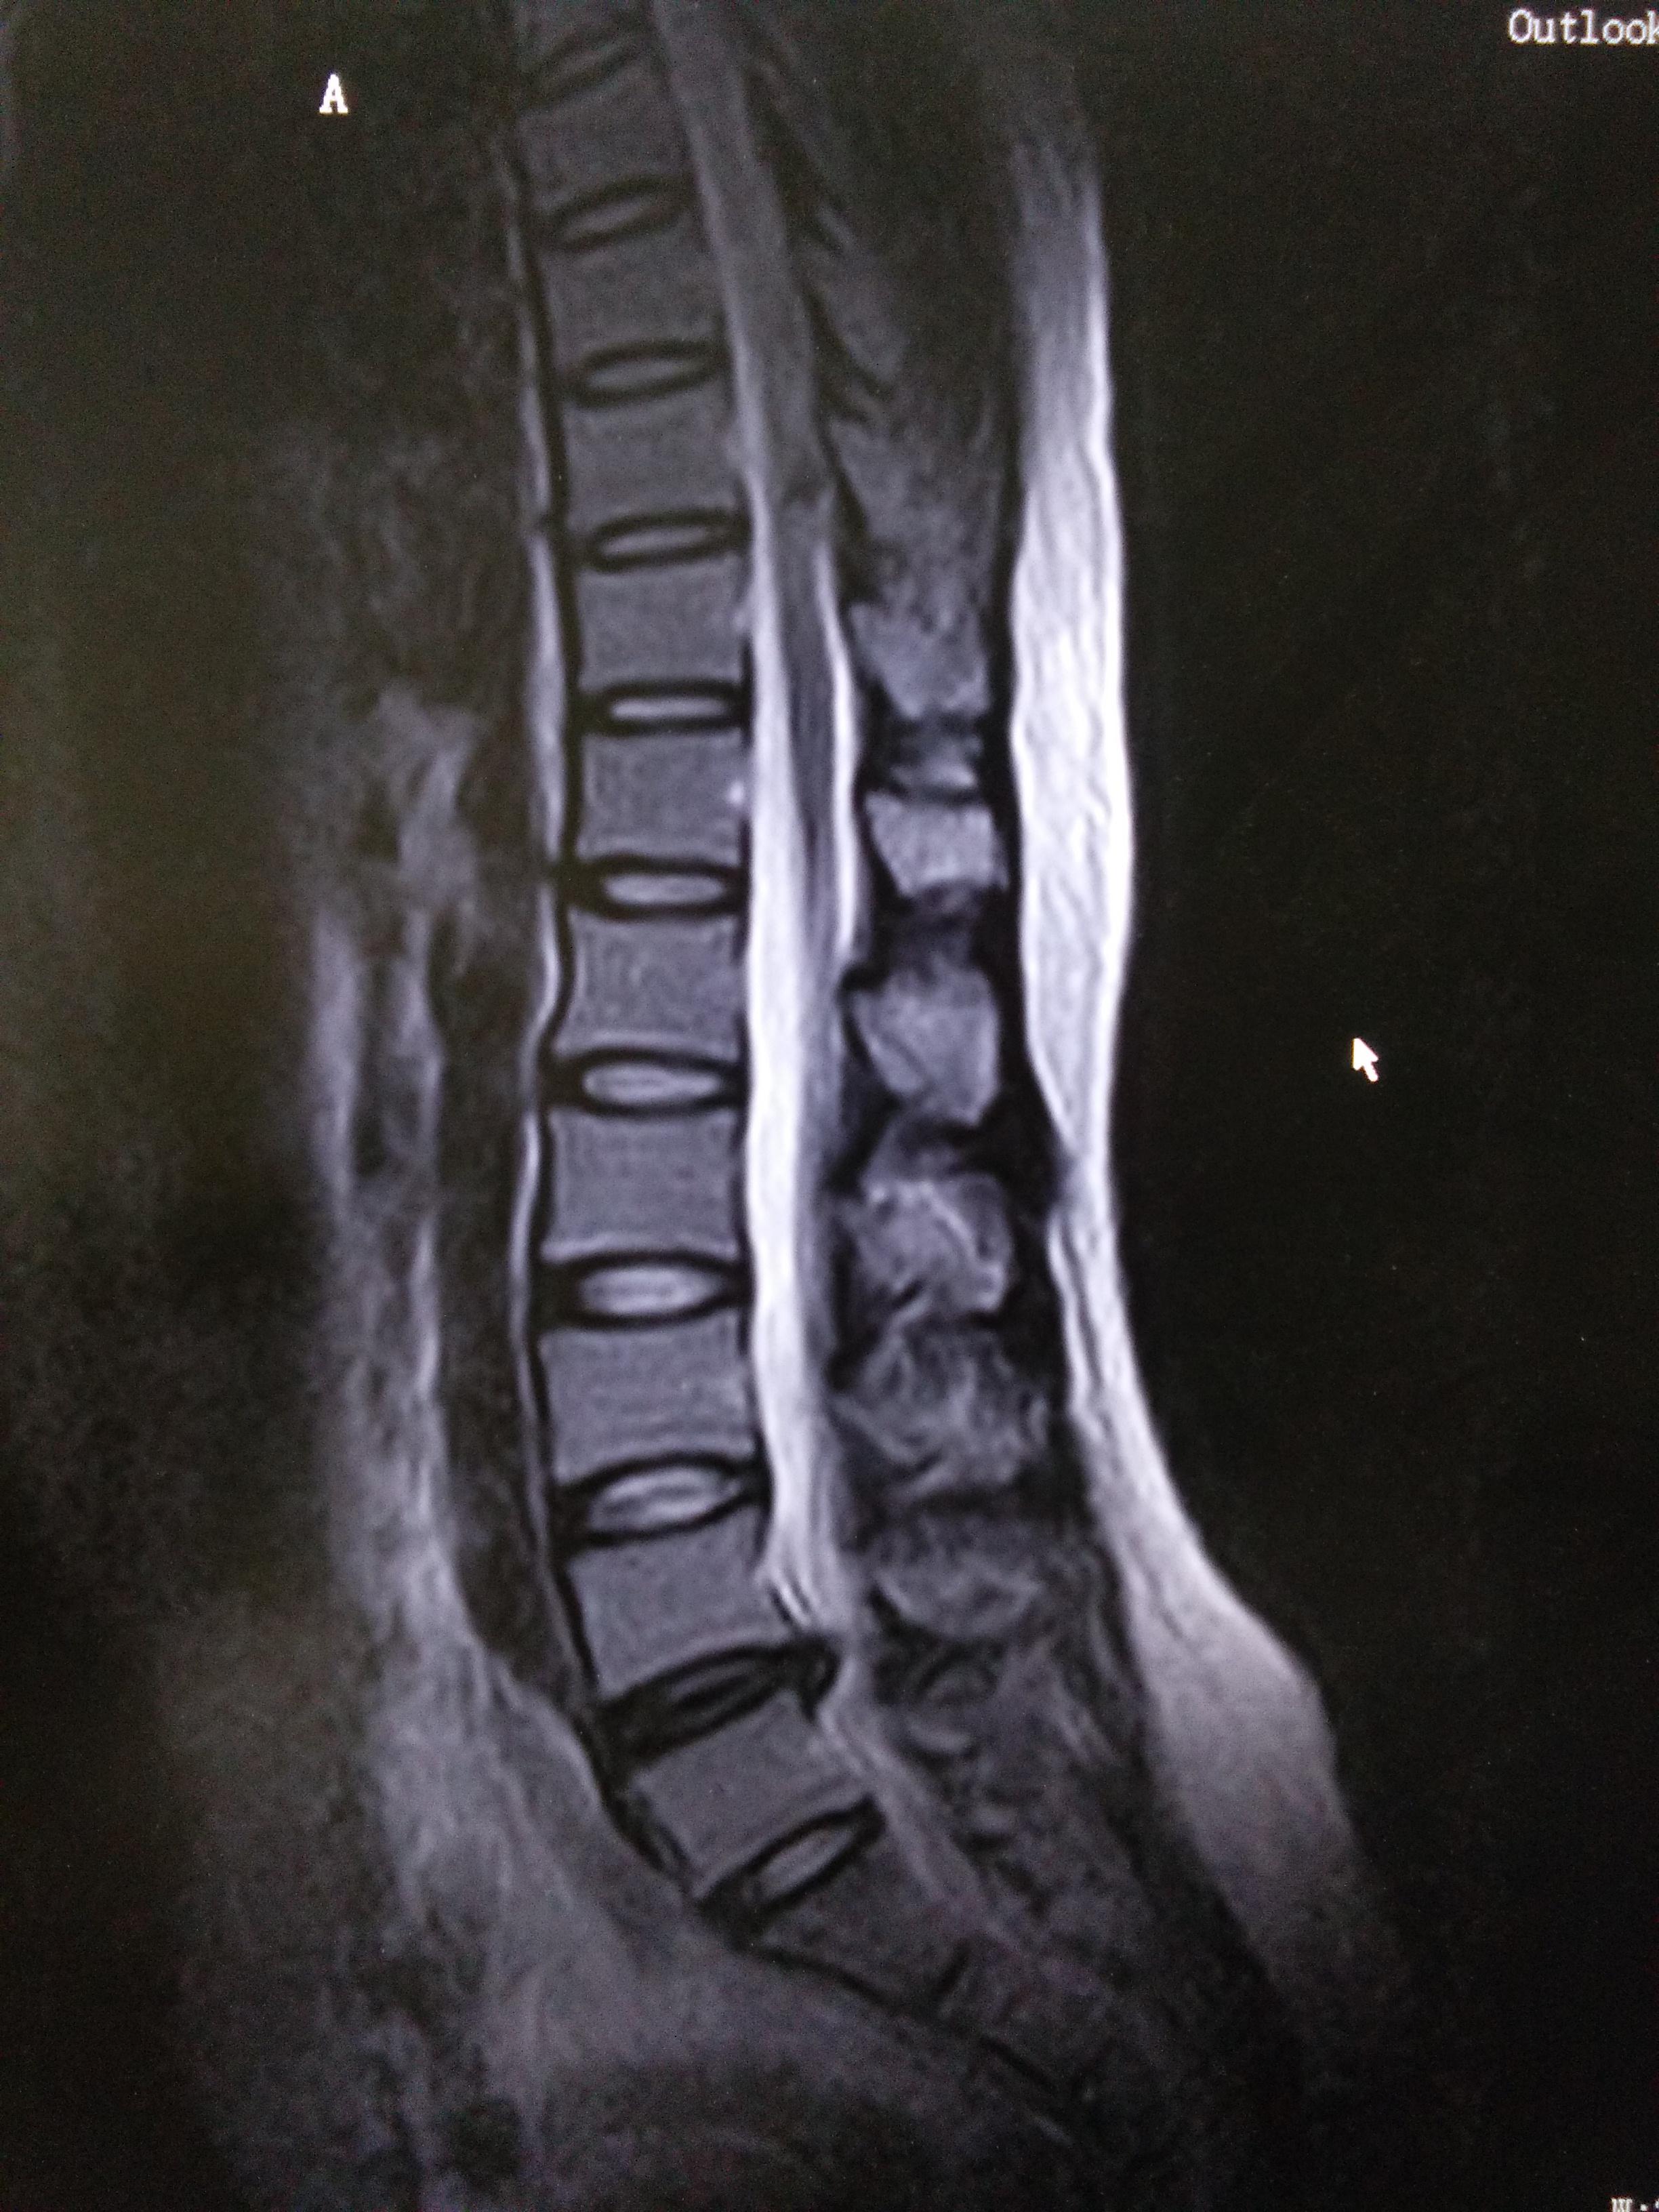

腰間盤問(wèn)題是一種常見的健康問(wèn)題,可能導(dǎo)致疼痛、不適和活動(dòng)受限,許多人尋求快速有效的解決方案以減輕癥狀,本文將介紹一種三天內(nèi)可以治好腰間盤問(wèn)題的方法,幫助您緩解不適,恢復(fù)健康。